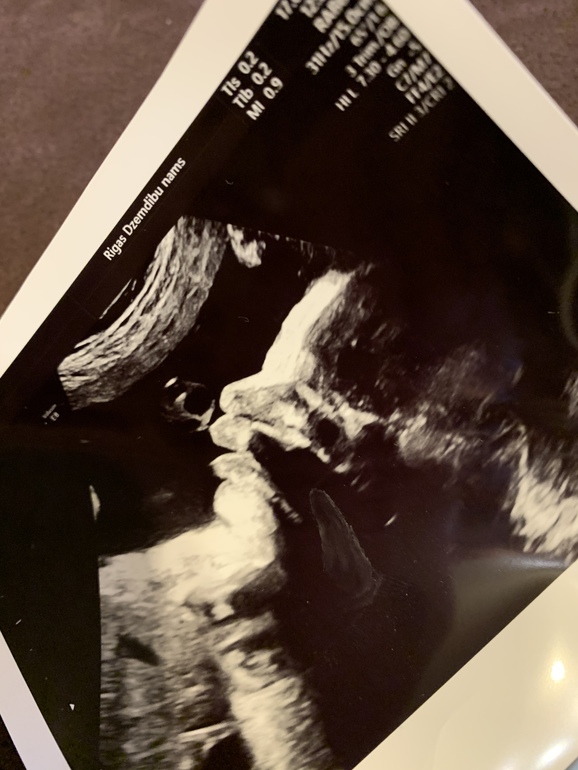

А тем временем идёт 31-я неделя. По плоду 32-я... Я больше не работаю. И понимаю, что лень напала))) Валяюсь дома, гуляю редко. Постоянно за рулем. А надо бы чаще бывать на свежем воздухе. Сегодня была на УЗИ. Плод, по всем параметрам соответствует 33 полным неделям! Опять ждать мне слонёнка))) Ну и фото нас на память. И просто и с узи.

Наша ножка))